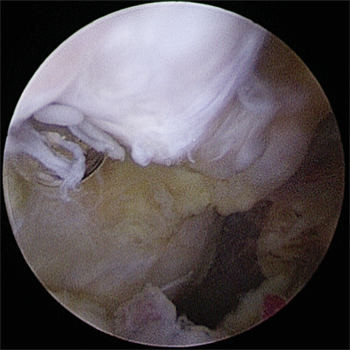

이미 관절 가동 범위에 제한이 온 팔꿈치 관절염은 뼈가 자라고

유리체 등이 관절면을 덮은 경우가 대부분으로 수술적 치료가 필요

관절내시경을 통해 자라난 뼈 조각과 관절 내 유리체를 제거하며

심한 경우 절개 수술이 함께 필요할 수 있습니다.